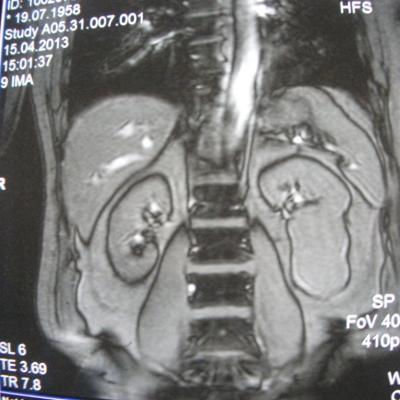

такое заключение: Левая почка: расположена обычно, увеличена, общими размерами около 13х5,5см. В области средней и нижней трети почки определяется объёмное образование неправильной формы, деформирующее наружный контур почки, распространяющиеся с чашечно-лоханочную систему. Опухоль имеет четкие неровные бугристые контуры с наличием псевдокапсулы, неоднородной структуры с признаками распада, максимальными размерами около 78,7х47х48мм